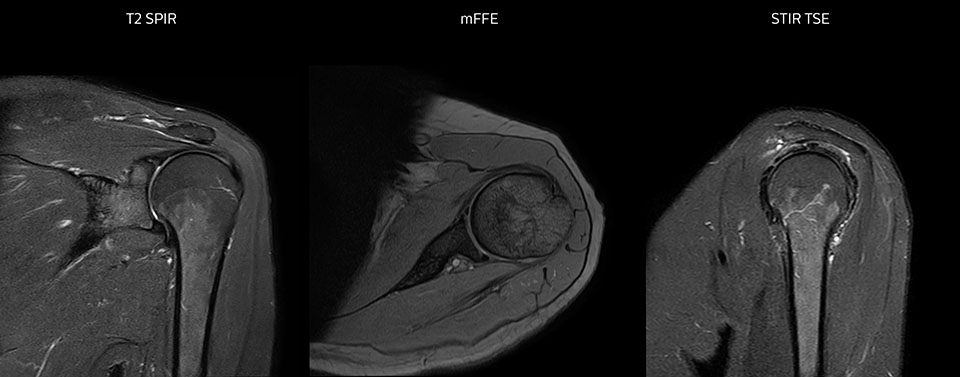

Die Prodiva Schulterspule ist sehr flexibel und hat eine grosse Abdeckung; dies erleichtert eine gute Positionierung, was wiederum zur ausgezeichneten Bildqualität und hohem SNR beiträgt, die wir in unseren Schulteruntersuchungen erreichen.

Scandauer: 2:55 Minuten, FOV: 160 mm, erfasste Voxel: 0,55 x 0,83 x 3,0 mm.

Scandauer: 04:19 Minuten, FOV: 160 mm, erfasste Voxel: 0,55 x 0,80 x 3,0 mm.

Scandauer: 02:50 Minuten, FOV: 160 mm, erfasste Voxel: 0,70 x 0,99 x 3,0 mm.